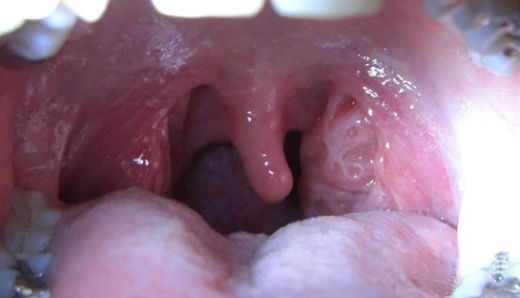

Sol bademcik şişmesi, genellikle boğazın arka kısmında yer alan lenfoid dokunun iltihaplanması veya enfekte olması durumudur. Bademcikler, bağışıklık sisteminin bir parçası olarak, vücut savunmasında önemli bir rol oynamaktadır. Bu durum, çeşitli etkenlerden kaynaklanabilir ve genellikle enfeksiyon belirtisi olarak ortaya çıkar.

Sol bademcik şişmesi, çeşitli belirtilerle kendini gösterebilir. Bu belirtiler şunları içerebilir: - Ağrı veya rahatsızlık hissi: Şişen bademcik, yutkunma sırasında ağrıya neden olabilir.

- Yutma zorluğu: Bademciklerin büyümesi, yiyeceklerin yutulmasını zorlaştırabilir.

- Boğazda tahriş: Şişmiş bademcikler, boğazda gıcırtı veya kaşıntı hissi yaratabilir.

Sol bademciğinizin şişmesi ve yutkunma zorluğu yaşamanız, genellikle bademcik iltihabı ile ilişkilendirilebilir. Bademciklerin iltihaplanması, çevresindeki dokulara da etki edebileceği için kulak ağrısı gibi belirtiler ortaya çıkabilir. Bu durum, bademciklerin ve çevresindeki lenf dokularının iltihaplanması sonucu gelişir.